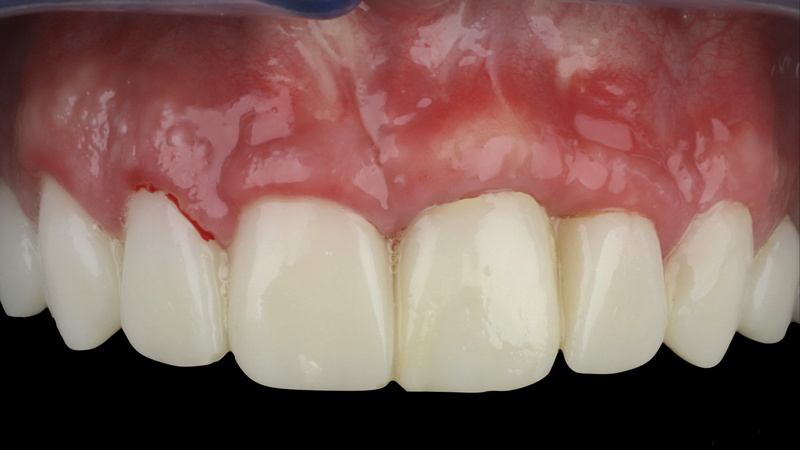

(2.) Preoperative retracted maxillary view of an implant-supported restoration at the site of tooth No. 9 demonstrating a peri-implant soft-tissue dehiscence extending approximately 3-mm apical to the gingival margin of tooth No. 8. Note the thin and erythematous marginal tissue evident at the zenith.

Figure 2

The patient in this case had undergone implant therapy at the site of tooth No. 9 and was restored with a cement-retained restoration more than 5 years prior. At presentation, the site demonstrated a peri-implant soft-tissue dehiscence that extended approximately 3-mm apical to the gingival margin of tooth No. 8. Thin and erythematous marginal tissue was evident at the zenith (Figure 2). The crown was removed, and a partial thickness flap was reflected using a papilla-sparing incision design. This revealed that the implant was positioned too far facially and that its body was visible through a very thin layer of bone (Figure 3 and Figure 4). The first objective of treatment was to minimize the facial extent of the emerging abutment and crown. To accomplish this, the facially positioned abutment and implant crown margin were both recontoured. The second treatment objective was to provide additional supracrestal soft tissue that would more adequately maintain the peri-implant margin. The tuberosity was selected as a donor site due to its dense, high-quality connective tissue, low propensity for shrinkage, and association with minimal patient discomfort. Once the graft was secured (Figure 5 through Figure 7), the flap was coronally positioned (Figure 8). After a healing period of 2 weeks, the margin of tooth No. 9 exhibited an ideal position in relation to its contralateral counterpart and demonstrated increased soft tissue thickness (Figure 9). Three months postoperatively, further healing had improved the esthetics and the position of the margin had been maintained (Figure 10).